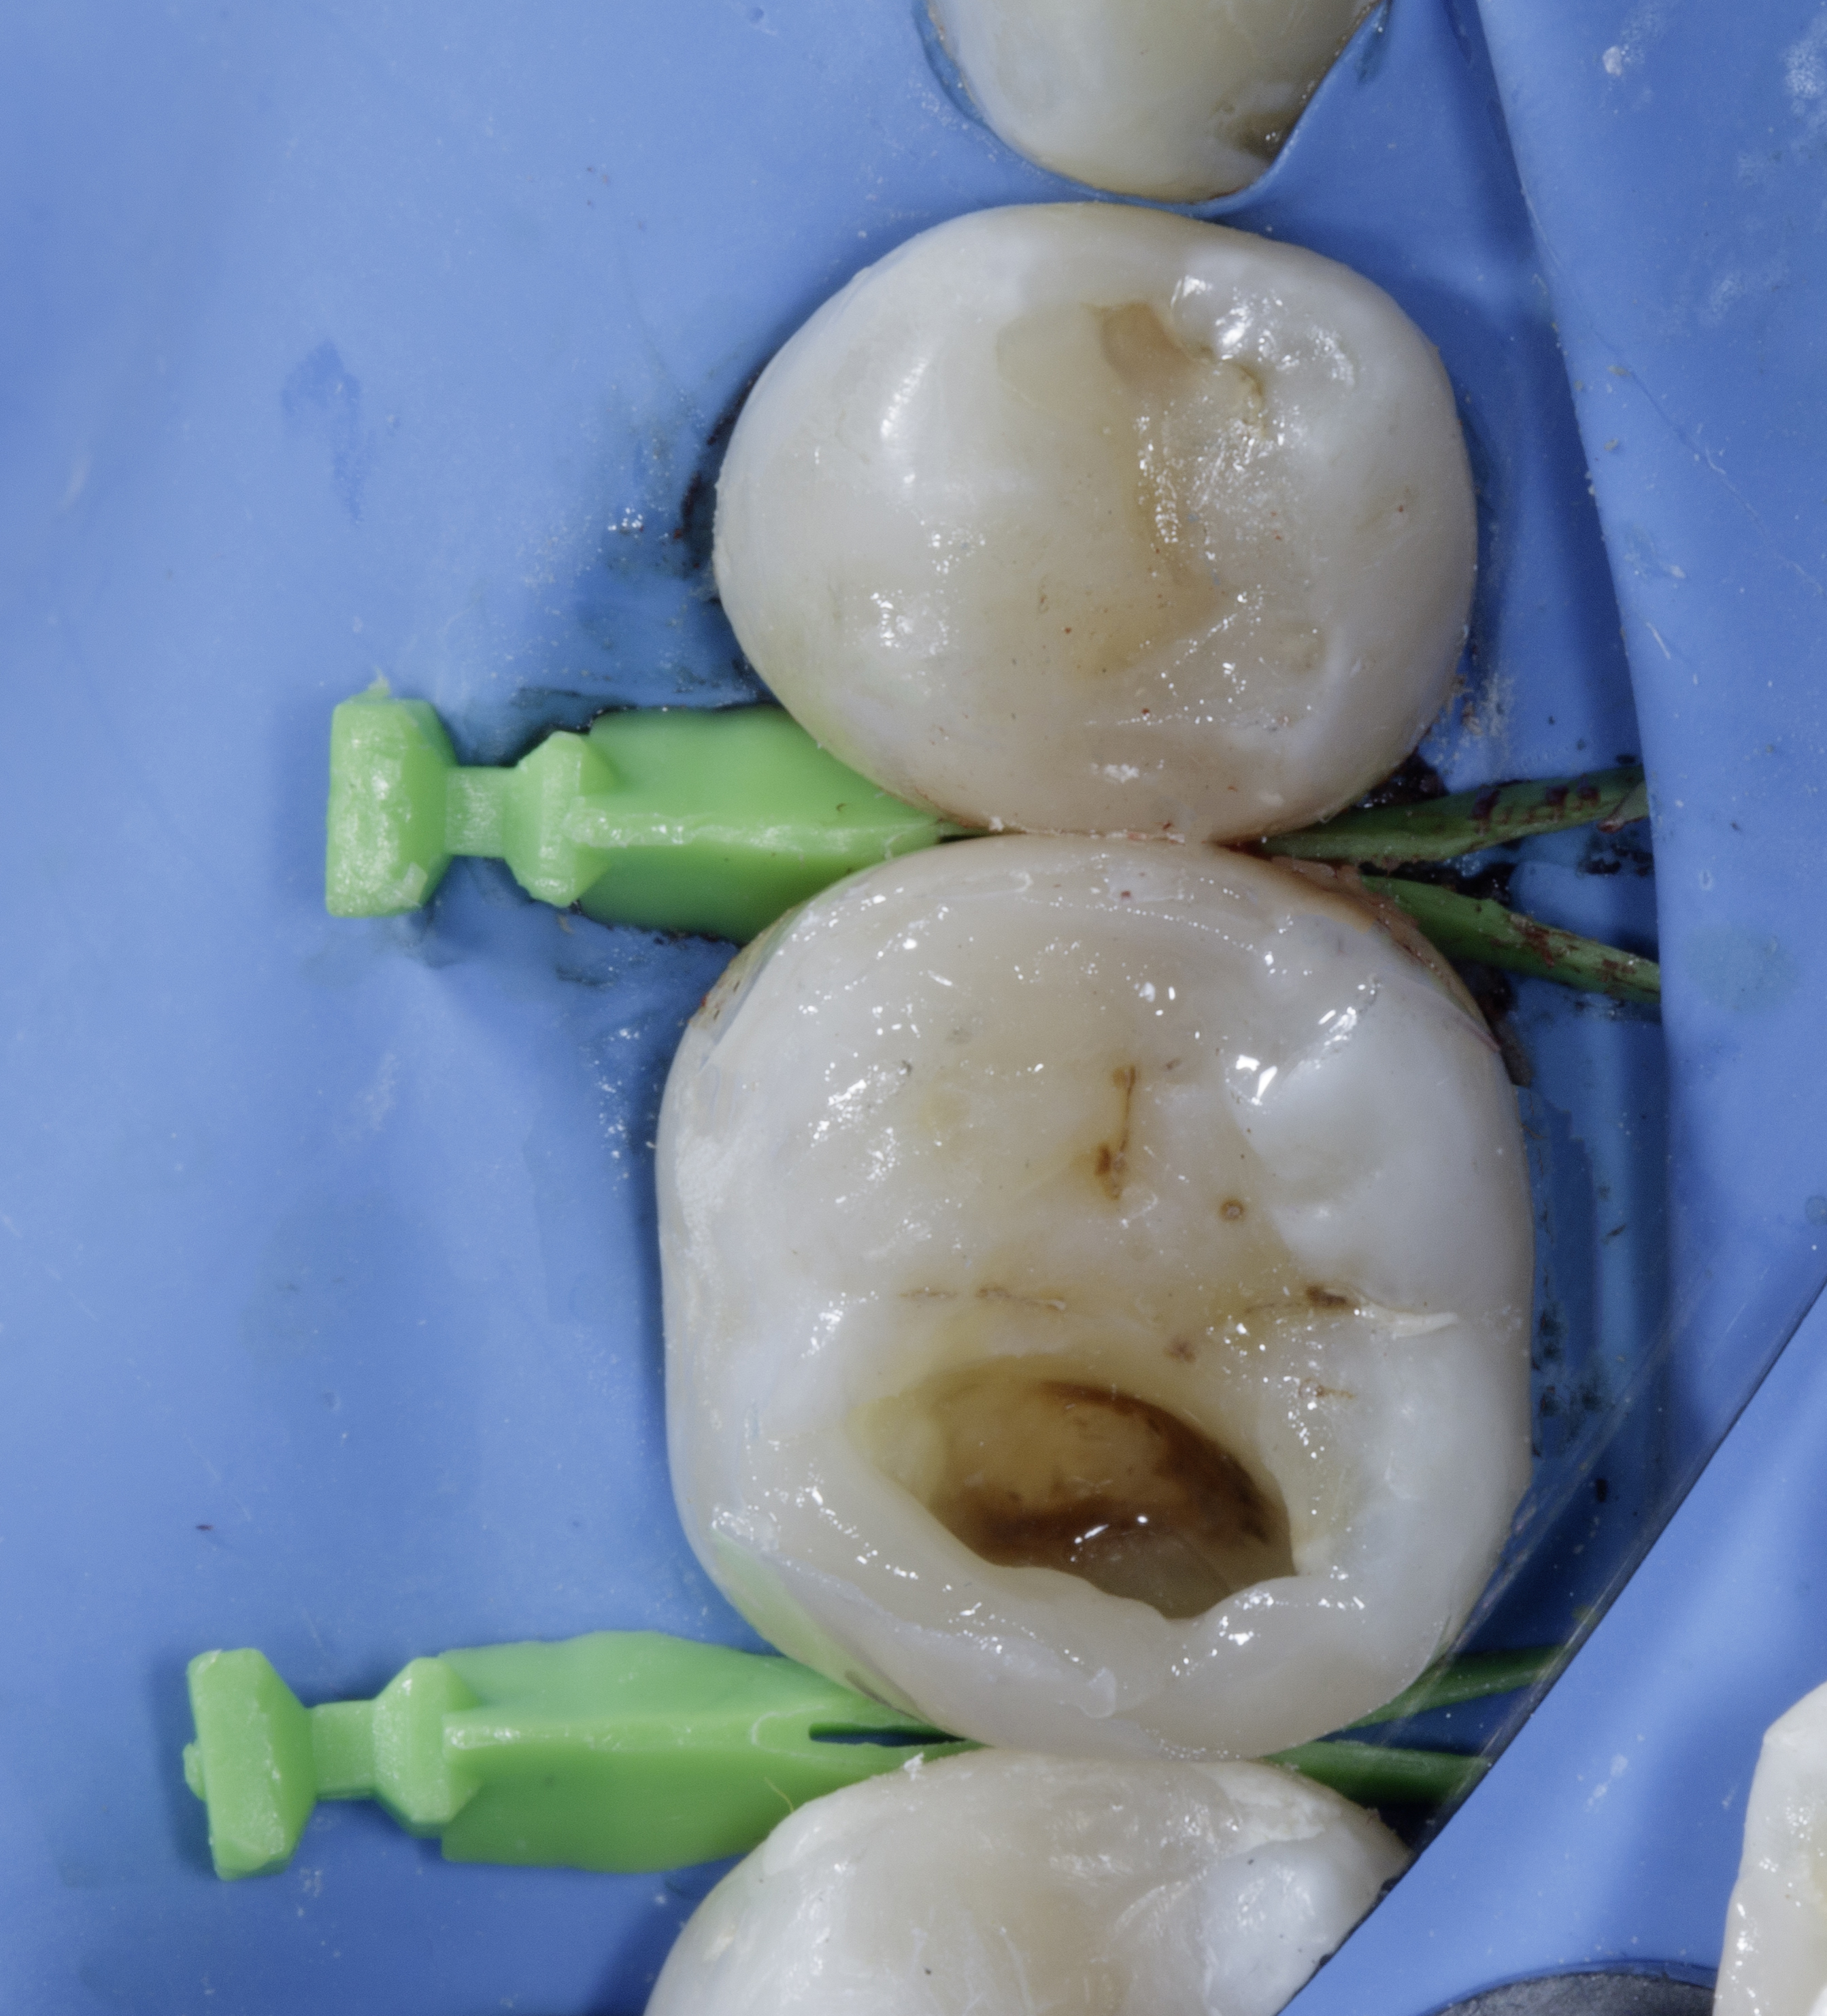

A 28-year-old woman presented to our office with complaints of sensitivity to cold temperatures and food impaction in her lower right quadrant. Her dental history revealed previous orthodontic treatment and multiple restoration failures in the same quadrant over the past 8-12 years.

Clinical examination showed significant mesio-occluso-distal (MOD) defects and Class 2 affecting teeth from #45 to #48.

Tooth #45: A distal carious lesion is suspected, potentially secondary to the adjacent mesial defect observed on tooth #46. No existing restoration is noted in this region, however, early discoloration and anatomical concavity suggest demineralization.

Tooth #46: Clinical examination revealed a mesial proximal carious defect with complete loss of the marginal ridge. On the distal aspect, an old composite restoration was observed, appearing underfilled and extended onto the occlusal surface. Evident marginal leakage and localized chipping were present along the restoration interface. Additionally, unsupported enamel was noted on the distobuccal cusp, indicating structural compromise and the risk of cusp fracture.

Tooth #47: An existing occlusal composite restoration demonstrated marginal discoloration and leakage. The distal surface exhibited a composite material of a different shade and texture, suggestive of a restoration placed at a later date. Lack of a defined marginal ridge resulted in an improper proximal contact. On the mesial surface, dark discoloration contiguous with the existing mesial pit composite indicated the presence of a recurrent or active Class II carious lesion.

Tooth #48: The mesial aspect showed dark discoloration extending into the existing mesial pit composite restoration, consistent with a developing or recurrent Class II carious lesion.

Bitewing radiograph confirmed the presence of multiple MOD / Class II carious lesions corresponding to the clinical findings. None of the defects demonstrated radiographic proximity to the pulp.

Figure 1. Multiple defects starting from tooth #45 to #48 as described above.Figure 2. Multiple class 2 defects starting from tooth #45 to #48 with loss of ideal contacts and contours.